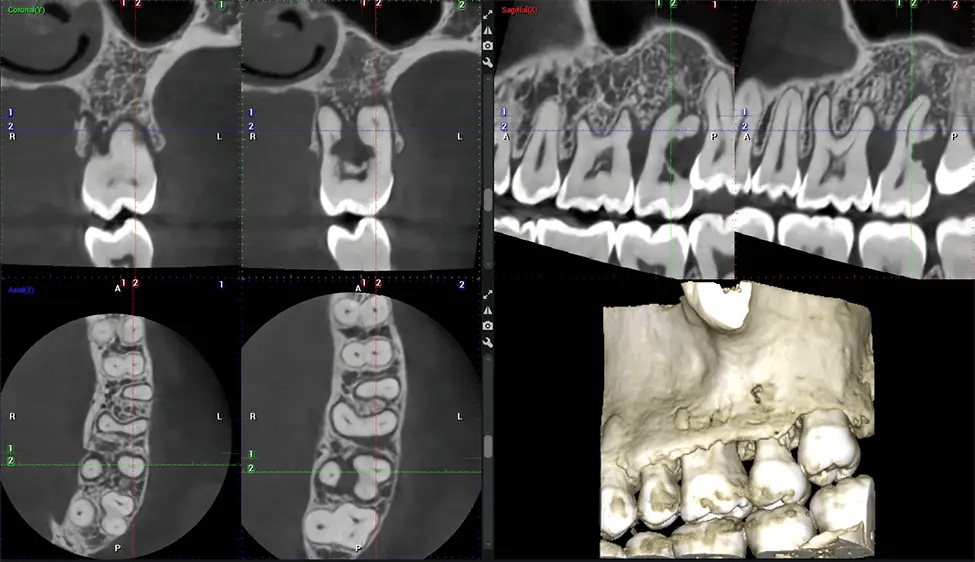

Cone Beam Computed Tomography (CBCT) is an advanced imaging technique used in dentistry and maxillofacial surgery to obtain detailed 3D images of the oral and maxillofacial structures. At Dr G Dental Studio, our CBCT scanners utilize a cone-shaped X-ray beam and a specialized detector to capture images from different angles. A computer then combines these images to create a 3D representation of the patient’s oral anatomy.

This 3D scan, called cone beam computed tomography, gives your dentist a more complete image of your oral anatomy and disease processes than a traditional X-ray. Unlike conventional X-rays, which capture a 2D image of your mouth from various angles, a 3D scan takes multiple digital X-rays for one image. It provides a complete view of your jaw, teeth, nerves, and soft tissues. This enhanced view allows dentists to detect minor issues not visible in traditional 2D scans, such as impacted wisdom teeth or bone fractures in the sinus cavity.

There are many benefits to using CBCT technology, especially compared to the traditional 2D X-ray format. One of the most significant advantages of CBCT scans is that they provide much more information than traditional X-rays. A scan lets your dentist see images from all angles of your jaw and mouth, including your sinuses, nasal cavity, cheekbones, and other surrounding areas. This added information helps your dentist craft a comprehensive treatment plan that addresses all aspects of your oral health.

Another significant benefit is that 3D imaging provides more precise images of your bone structure. These images are more detailed, providing you with a more accurate diagnosis. An accurate diagnosis means better treatment for you.

Planmeca Viso G7 CBCT ( Cone Beam CT Scan ) is designed to surpass the demands of industry leaders, specialists, and large institutions. It’s has a large ø25×30 cm sensor with four built-in cameras. It can capture unlimited volume sizes from a ø3×3 cm to a ø30x30cm volume capturing the skullcap through C7 on the cervical spine. The Planmeca Viso G7 offers the industry’s largest single volume scan of ø30×19 cm. It’s poised to handle advanced imaging modalities such as Planmeca ProFace® and Planmeca 4D™ Jaw Motion technology. The occipital head support allows an unimpeded view of facial tissue.